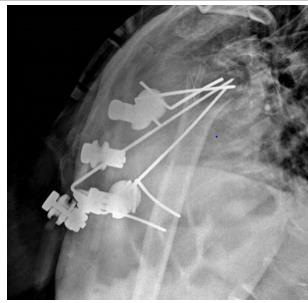

A 69-year-old woman came to ER of Poliambulanza of Brescia in October 2019. X-rays were obtained. Fracture involved proximal humerus of the right, dominant, upper arm. The fracture was 11C3.1 according to AO classification. At first, the fracture was treated with an external. fixation using a Galaxy EF in the first twenty-four hours. The EF was removed after one month because of the loss of reduction with displacement of the fracture. Physio- kinesitherapy was indicated but she was unable to underwent to treatment. She was lost at follow -up for several months due to COVID-19 pandemic and the social limitations that resulted. After 7 months, Xrays showed a dislocated nonunion of proximal humerus with necrosis of the head. She complained shoulder pain with passive elevation of 40° and scapular dyskinesia. In March 2021 she was listed for a reverse shoulder arthroplasty. During the surgery, Synovasure test and white blood cell count were performed: both tested negatives. A cemented trauma stem “Equinoxe” by Exactech number 8 mm was applied with a standard baseplate fixed with three screws of 26, 18, 18 mm. External rotators were reinserted, and range of motion (ROM) was good at three months follow-up.